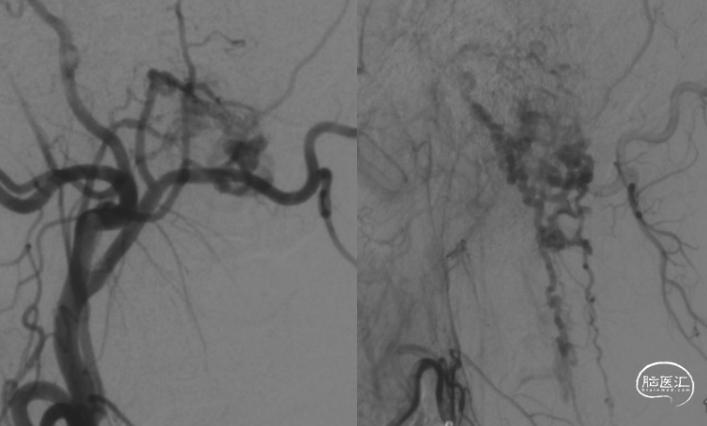

男性,34岁。主因“头痛、头晕伴头颈部麻木40天余”入院。既往病史无特殊。入院查体可见右侧病理征阳性,右侧C2-4前感觉减退。外院检查提示高位颈髓水肿,髓周血管瘤空影。

枕骨大孔区硬膜动静脉瘘;供血:耳后动脉、咽升动脉、椎动脉脊膜支。

手术过程及术后恢复顺利。术后原有症状明显缓解。术后复查造影提示瘘消失。